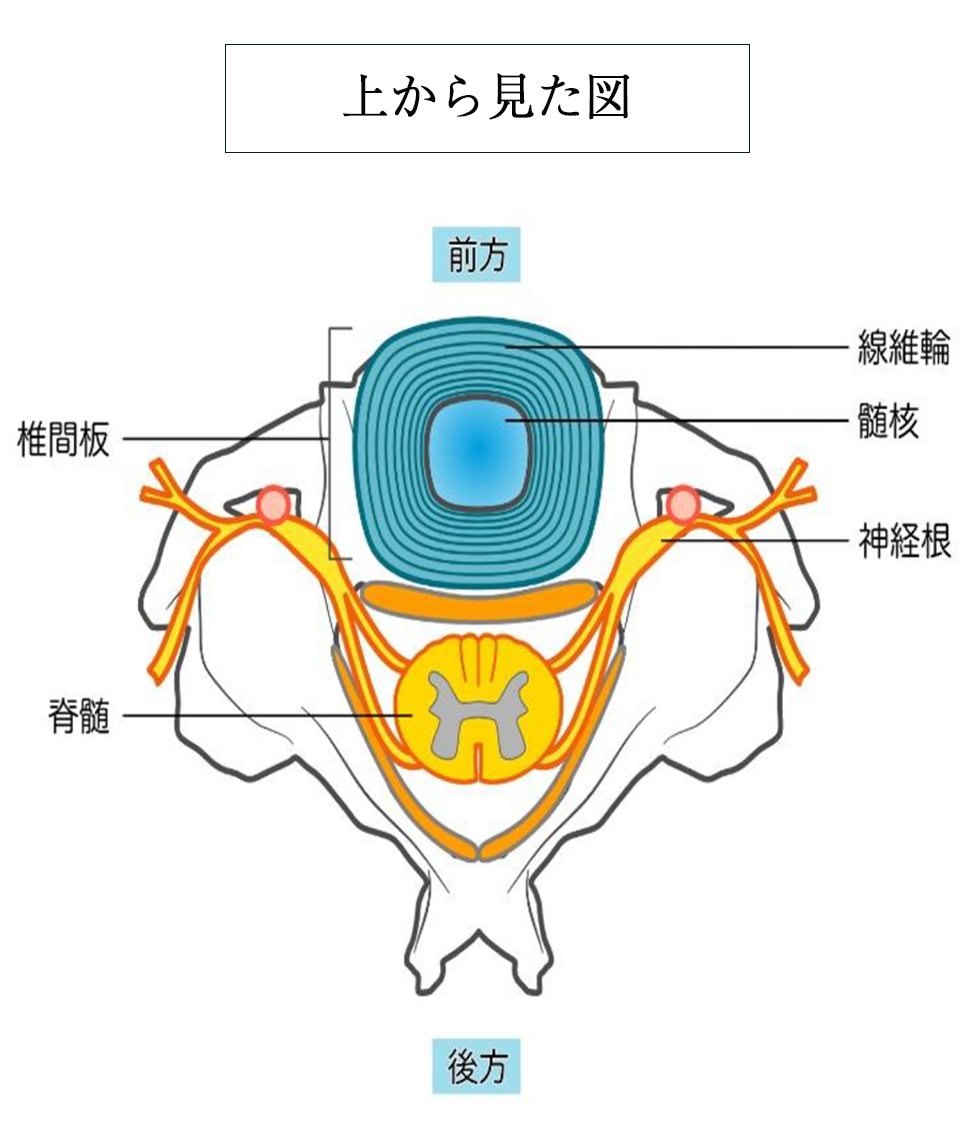

さらに椎骨と椎骨との間には椎間板という組織があり、椎骨にかかる衝撃を和らげるクッションのような役割を果たしています。

■頸椎椎間板ヘルニア

頸椎を構成する椎骨と椎骨の間には椎間板というクッション性のある組織が存在します。何らかの原因でその椎間板が飛び出し、神経を圧迫するのが椎間板ヘルニアです。